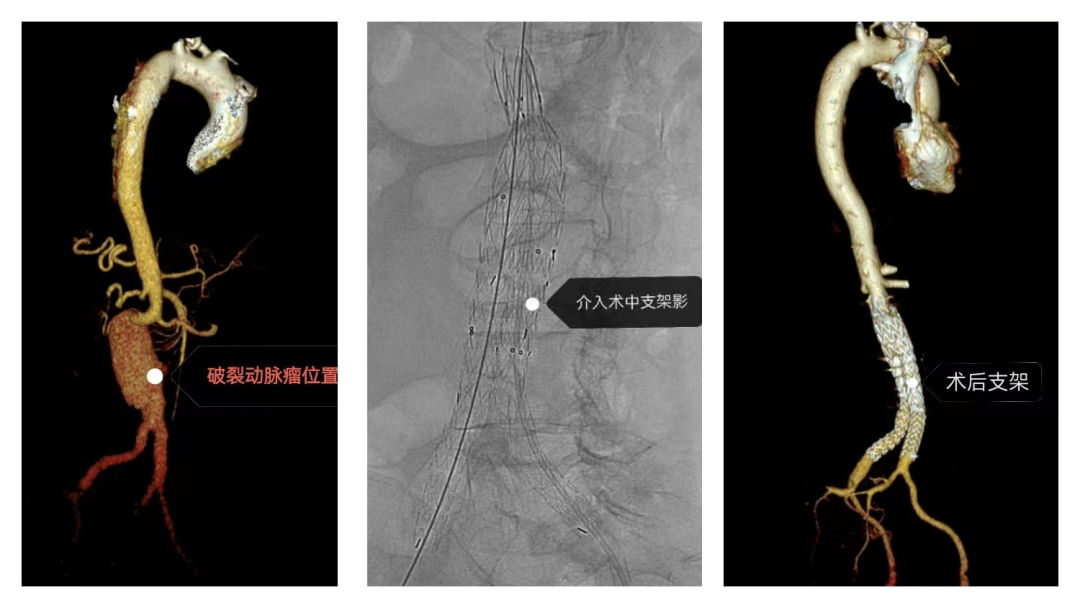

近日,45岁的患者黄女士因腹主动脉瘤破裂,性命垂危。关键时刻,我市医共体的高效协同救治体系发挥巨大作用,患者被紧急转送到兴宁市人民医院,心胸外科团队及时开展手术抢救,患者生命得以成功挽救。 6月25日,伴随着120清脆的鸣笛声,兴宁市人民医院急诊科接到了转送来的患者黄女士,患者因下腹部撕裂样疼痛入院,接诊医生认真询问病史及查体,警觉发现病情复杂,在行全主动脉CTA检查时,迅速联系医务科启动“绿色通道”,请心胸外科、重症医学科、麻醉科急会诊。CTA图像显示,患者腹主动脉瘤已经出现破裂,腹腔大量积血,血管条件极差,生命危在旦夕。心胸外科曾伟生教授和闫玉生教授在查看报告后,考虑病情紧急,必须立即手术,与患者及家属充分沟通后,决定立即行腹主动脉瘤覆膜支架腔内隔绝术封堵破口。 手术难度大、风险高,闫玉生教授率领心胸外科团队,联合重症医学科、急诊科、放射科、介入室、麻醉科等多个学科,研究讨论手术方案、准备手术,经过紧张周密的术前准备工作,在当天下午就为患者开展手术。在麻醉科行气管插管全麻后行腹主动脉瘤覆膜支架隔绝术+双侧髂总动脉腔内隔绝术,手术中,黄女士因破裂口位于主干道上,出血量大,一度出现血压及心率持续下降的危情,闫玉生教授及其团队有条不紊,想尽办法维持患者血压心率稳定,并精准地释放支架阻断了破口,争分夺秒与“死神”赛跑,在心胸团队和多学科的通力合作下,经过6个多小时手术,患者成功脱离生命危险。 经过半个月的悉心治疗,黄女士在7月10日顺利出院。“术后的康复很关键,出院后至少三个月到半年不能剧烈运动,注意休息,保持良好生活习惯,记得按时随访复查……“”闫教授对黄女士及家属仔细叮嘱注意事项。 据介绍,腹主动脉瘤破裂(rAAA)是一种致死率相当高的疾病,死亡率高达85%,约2/3的患者在到达医院前死亡,对于存活下来接受手术的患者,围手术期死亡率仍高达41%~48%,被医学界称为藏在人体腹腔的“定时炸弹”。闫教授提醒,大多数腹主动脉瘤患者在血管破裂之前几乎没有症状,或者轻微腹痛不适,很容易被忽视,预防腹主动脉瘤要养成良好的生活习惯,积极控制高血压、高血脂、动脉硬化等危险因素,戒烟等。一旦发现腹主动脉瘤,应积极控制血压,稳定情绪,避免用力咳嗽、血压波动等,以最大限度降低动脉瘤的破裂风险,同时应就近及时就医。 “这次成功的转诊救治案例,展现了我市医共体的高效协同救治能力,也凸显了医共体总院特聘专家教授团队人才资源和技术优势,在这种机制联动配合下,医疗服务跑出了“加速度”,患者在家门口就能得到更及时更精准的救治。”市人民医院名誉院长、特聘教授曾伟生说。 实施此类比肩省级大型医院技术的高难度手术,在兴宁市人民医院已不是个例。据统计,2020年以来,该院心胸外科已成功完成二尖瓣置换术、三尖瓣成形术、主动脉弓置换术等复杂四级手术100多例。介入治疗水平上新台阶,每年开展介入手术1300多例,其中心脏介入手术1200多例、外周介入手术100多例。 学科和人才的发展推动医院走上快速发展之路。近年来,兴宁市人民医院坚持“科技兴院、人才强院”的医院战略管理方针,以二甲复审为契机,以创建三级医院为抓手,以学科建设和人才培养为导向,通过“筑巢引凤”“借鸡生蛋”“人才共享”等方式,走出了一条医院可持续发展、高质量发展之路。医院2022年4月入选国家“千县工程”县医院综合能力提升工作县医院名单,取得了2022年全省263家二级综合医院中DRGs综合评价排名第一名。有神经内科、神经外科、普通外科、全科医学科、放射科、医学检验科等6个市级临床重点专科。现有特聘专家教授19人。胸痛中心于2023年2月通过广东省胸痛中心协会认证。创伤中心于2024年7月通过广东省三级创伤中心建设单位评审。呼吸与危重症医学科于2021年通过国家呼吸与危重症医学科(PCCM) 规范化建设项目认证优秀单位,2022年还荣获第九届“县域医疗榜样力量”系列评选奖项“学科建设卓越奖”。 “我院作为医共体总院,充分发挥龙头纽带作用,积极加强与基层医院联动合作,通过专家下沉、技术帮扶、人才培养、信息互通等方式,实现了资源共享,互赢共惠,联动发展,努力构建“基层首诊、双向转诊、急慢分治、上下联动”的分级诊疗新格局。”市人民医院负责人刘示表示,下一步,总院将持续推动医院各项工作向纵深发展,做强医共体总院龙头,加强学科建设、人才培养,全面提升医疗技术水平和服务能力,让优质医疗资源惠及更多群众,推动“百千万工程”在卫生健康领域落地落实。